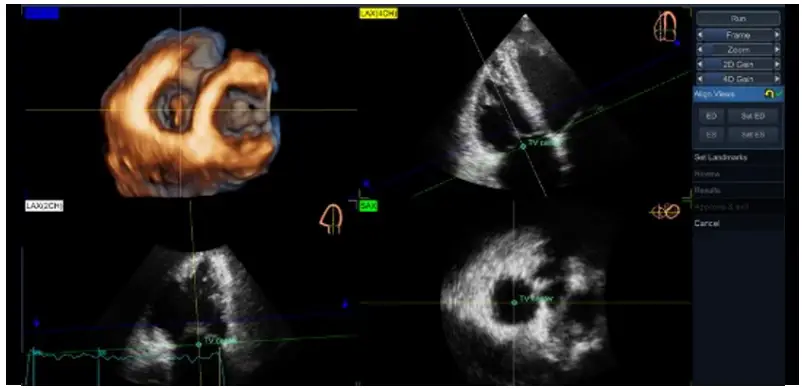

Align Views: - Place the TV center landmark at the center of TV annulus in both 4-chamber [LAX(4CH) – yellow] and the orthogonal view [LAX(2CH)) – white], as well as in the short-axis (SAX– green) view.

- Position the longitudinal axis of the RV to intersect the RV apex and the center of TV annulus in both 4CH and 2CH, as indicated in the miniature drawings shown in the right upper corner of each image

- The transversal green plane should be positioned at the TV annulus level, crossing approximately the leaflet hinges in each view (due to the saddle shape of the annulus, the plane position cannot be perfectly aligned with the 4 annulus points in both views simultaneously).

- The blue plane corresponds with the rendered SAX3D (upper left image) and it is generally recommended to be positioned on the ventricular side of the TV for TTE and on atrial side for TEE (Figure 3), close to the valve, to allow a proper visualization of the TV leaflet morphology and its spatial relationship with surrounding anatomic structures to facilitate the orientation of the user (Figure 4)

Figure 4. TV quad view showing the alignment of the views and planes with 4D Auto TVQ on a transthoracic TV data set